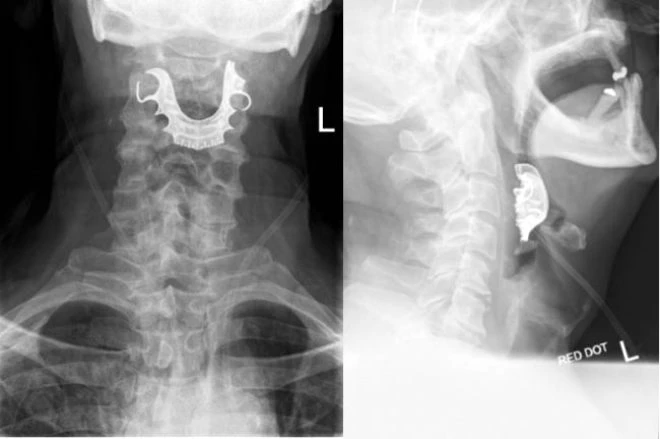

Əməliyyat zamanı protez dişləri boğazına düşdü